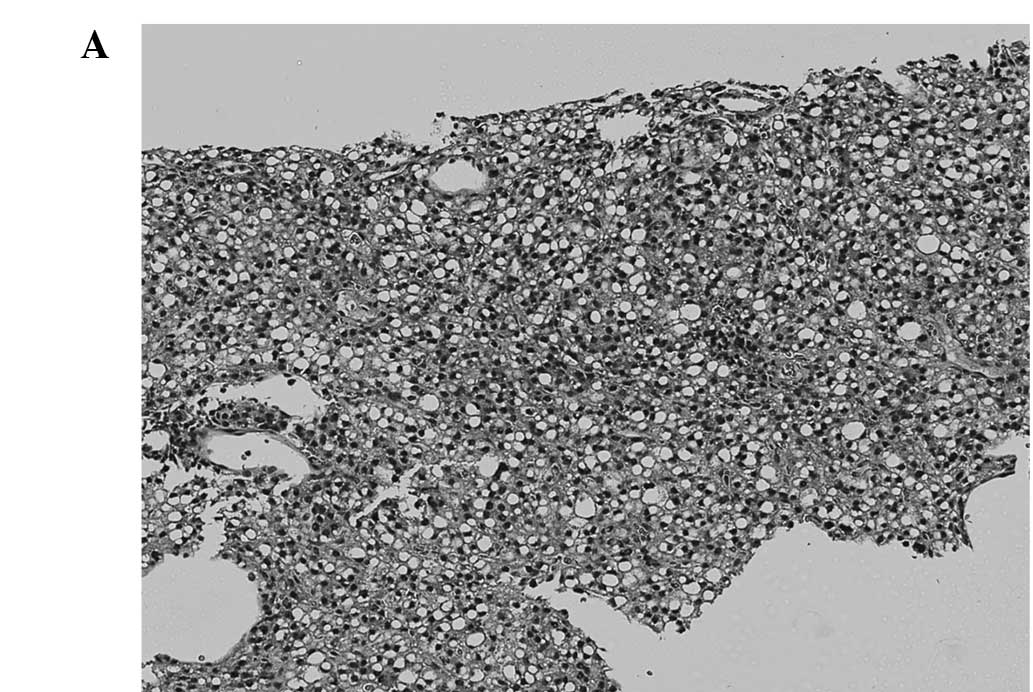

Six patients who developed local recurrence underwent tumor biopsy before starting RFA. In 5 of these 6 patients, dedifferentiation of HCC was observed. One well-differentiated HCC changed to poorly differentiated HCC (Fig. 1), three well-differentiated HCCs changed to moderately differentiated and one well-to-moderately differentiated HCC changed to moderately differentiated. Only one moderately differentiated HCC was unchanged after RFA therapy (Table V).

Comparison of pathological findings between a resected local recurrence after RFA and the needle biopsy specimen obtained before RFA (case 1). (A,B) Needle biopsy specimen of HCC obtained before RFA is well differentiated. (C,D) Resected specimen of the recurrent tumor. Besides necrosis due to RFA, a massive growth of poorly differentiated tumor cells is observed.